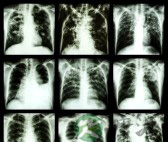

小编导读:结核病是一种周身性的疾病,由于它是最容易经呼吸道传染,最初发生的结核病,常常是在肺部,因而结核病以肺结核最为常见。在病发展过程中,结核病可以从肺部在播散到身体的其他部分。近年来,随着结核病发病率的增高,肺结核会传染吗,肺结核如何治疗,成为人们关注的热点问题。……

结核病是一种周身性的疾病,由于它是最容易经呼吸道传染,最初发生的结核病,常常是在肺部,因而结核病以肺结核最为常见。在病发展过程中,结核病可以从肺部在播散到身体的其他部分。近年来,随着结核病发病率的增高,肺结核会传染吗,肺结核如何治疗,成为人们关注的热点问题。